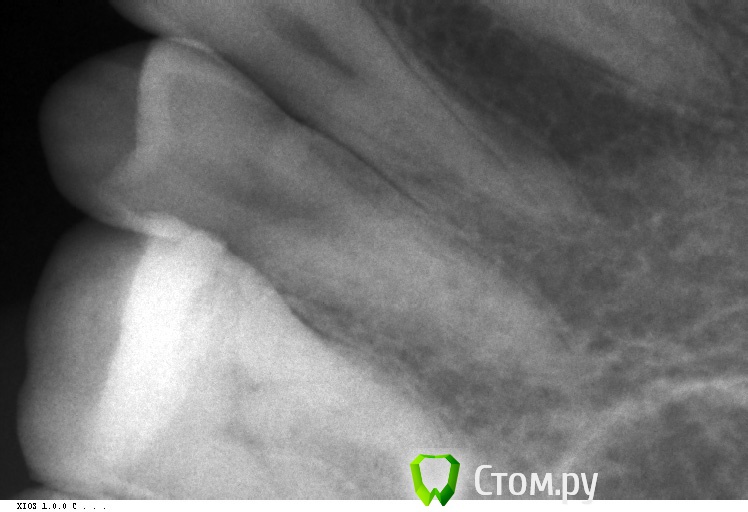

Барсук Опубликовано 12 марта, 2014 Поделиться Опубликовано 12 марта, 2014 (изменено) Добрый день уважаемые специалисты! Такая проблема... немного предыстории. Лет 15 назад верхнюю 6-ку заплобировали.В том году случился рецидив, заделали, получилась довольно большая пломба.Недавно в районе этого зуба стало иногда ныть, и как бы зуд такой, особенно после еды. Помогала чистка. И вот во время чистки нитью я обнуражил, что если пошерудить пальцем десну рядом с зубом - то он очень неприятно пахнет какой-то гнилью - тухлятиной, фу-фу-фу.Именно в районе этого зуба.Был у стамотолога, сделали снимки, он никаких паталогий не обнаружил, заметил только на снимке между зубов выступающую пломбу и зашлифовал, вдруг там остатки еды скапливаются. А вскрывать зуб пока смысла нет, тем более если вскрывать то придется уже депульпирвоать и скорее всего вкладку делать. Две недели прошло, все так же воняет десна.Когда промываю ирригатором в определенном месте между зубами есть заметная чувствительность.К слову сказать, ирригатор помогает на минуту. Потом снова если надавить-пошерудить пальцем - тот будет вонять.Но целом на холодное/горячее не реагирует. Есть мысли?Может к пародонтологу надо? Снимки по-моему не очень хорошие, но какие есть. прилагаю: Изменено 12 марта, 2014 пользователем Барсук Ссылка на комментарий

Zlata-doctor Опубликовано 12 марта, 2014 Поделиться Опубликовано 12 марта, 2014 Некорректная пломба медиальной поверхности? (контактный пункт, нависание) Окончательный диагноз-после осмотра и повторного снимка в другой проекции (или нескольких) Пока не вижу оснований для эндодонтического лечения ни по вашему описанию, ни по снимку. Думаю, что нужна хорошая пломба или вкладка (онлей-инлей) Ссылка на комментарий

Гарриевич Опубликовано 12 марта, 2014 Поделиться Опубликовано 12 марта, 2014 Надо сделать так, чтобы пища там не застревала, то есть сформировать хороший контакт между 5 и 6 зубами Ссылка на комментарий